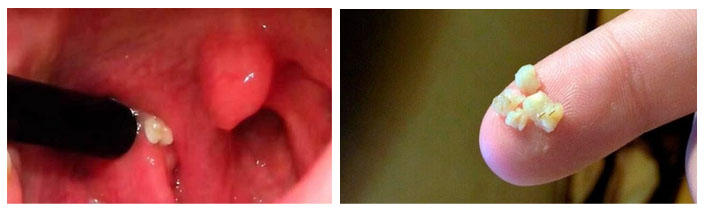

Хронический тонзиллит представляет собой длительное воспаление миндалин. При этой патологии образуются гнойные пробки в миндалинах, и заболевание часто протекает без повышения температуры и ухудшения общего самочувствия. Миндалины при этом становятся увеличенными, рыхлыми и могут иметь неравномерные размеры (одна миндалина может быть больше другой). Наблюдается постоянное покраснение краев дужек, их отечность, а также возможны сращения миндалин с дужками. В углублениях увеличенных миндалин могут формироваться казеозные пробки (или тонзиллолиты), которые выглядят как белые комки. Эти плотные образования, известные как «тонзиллитные камни», состоят из клеток эпителия, остатков пищи и продуктов фагоцитоза.

В нормальных условиях небольшие пробки при глотании самостоятельно удаляются из крипт. Однако при значительном увеличении миндалин, из-за сложной структуры крипт в более глубоких участках, пробки могут задерживаться. При присоединении бактериальной флоры возникает неприятный запах, и пациент может ощущать во рту белые комки с дурным запахом.

Казеозные пробки не представляют опасности, но могут вызывать дискомфорт. В некоторых случаях промывание миндалин дает лишь временное облегчение, и тогда прибегают к хирургическим методам лечения.